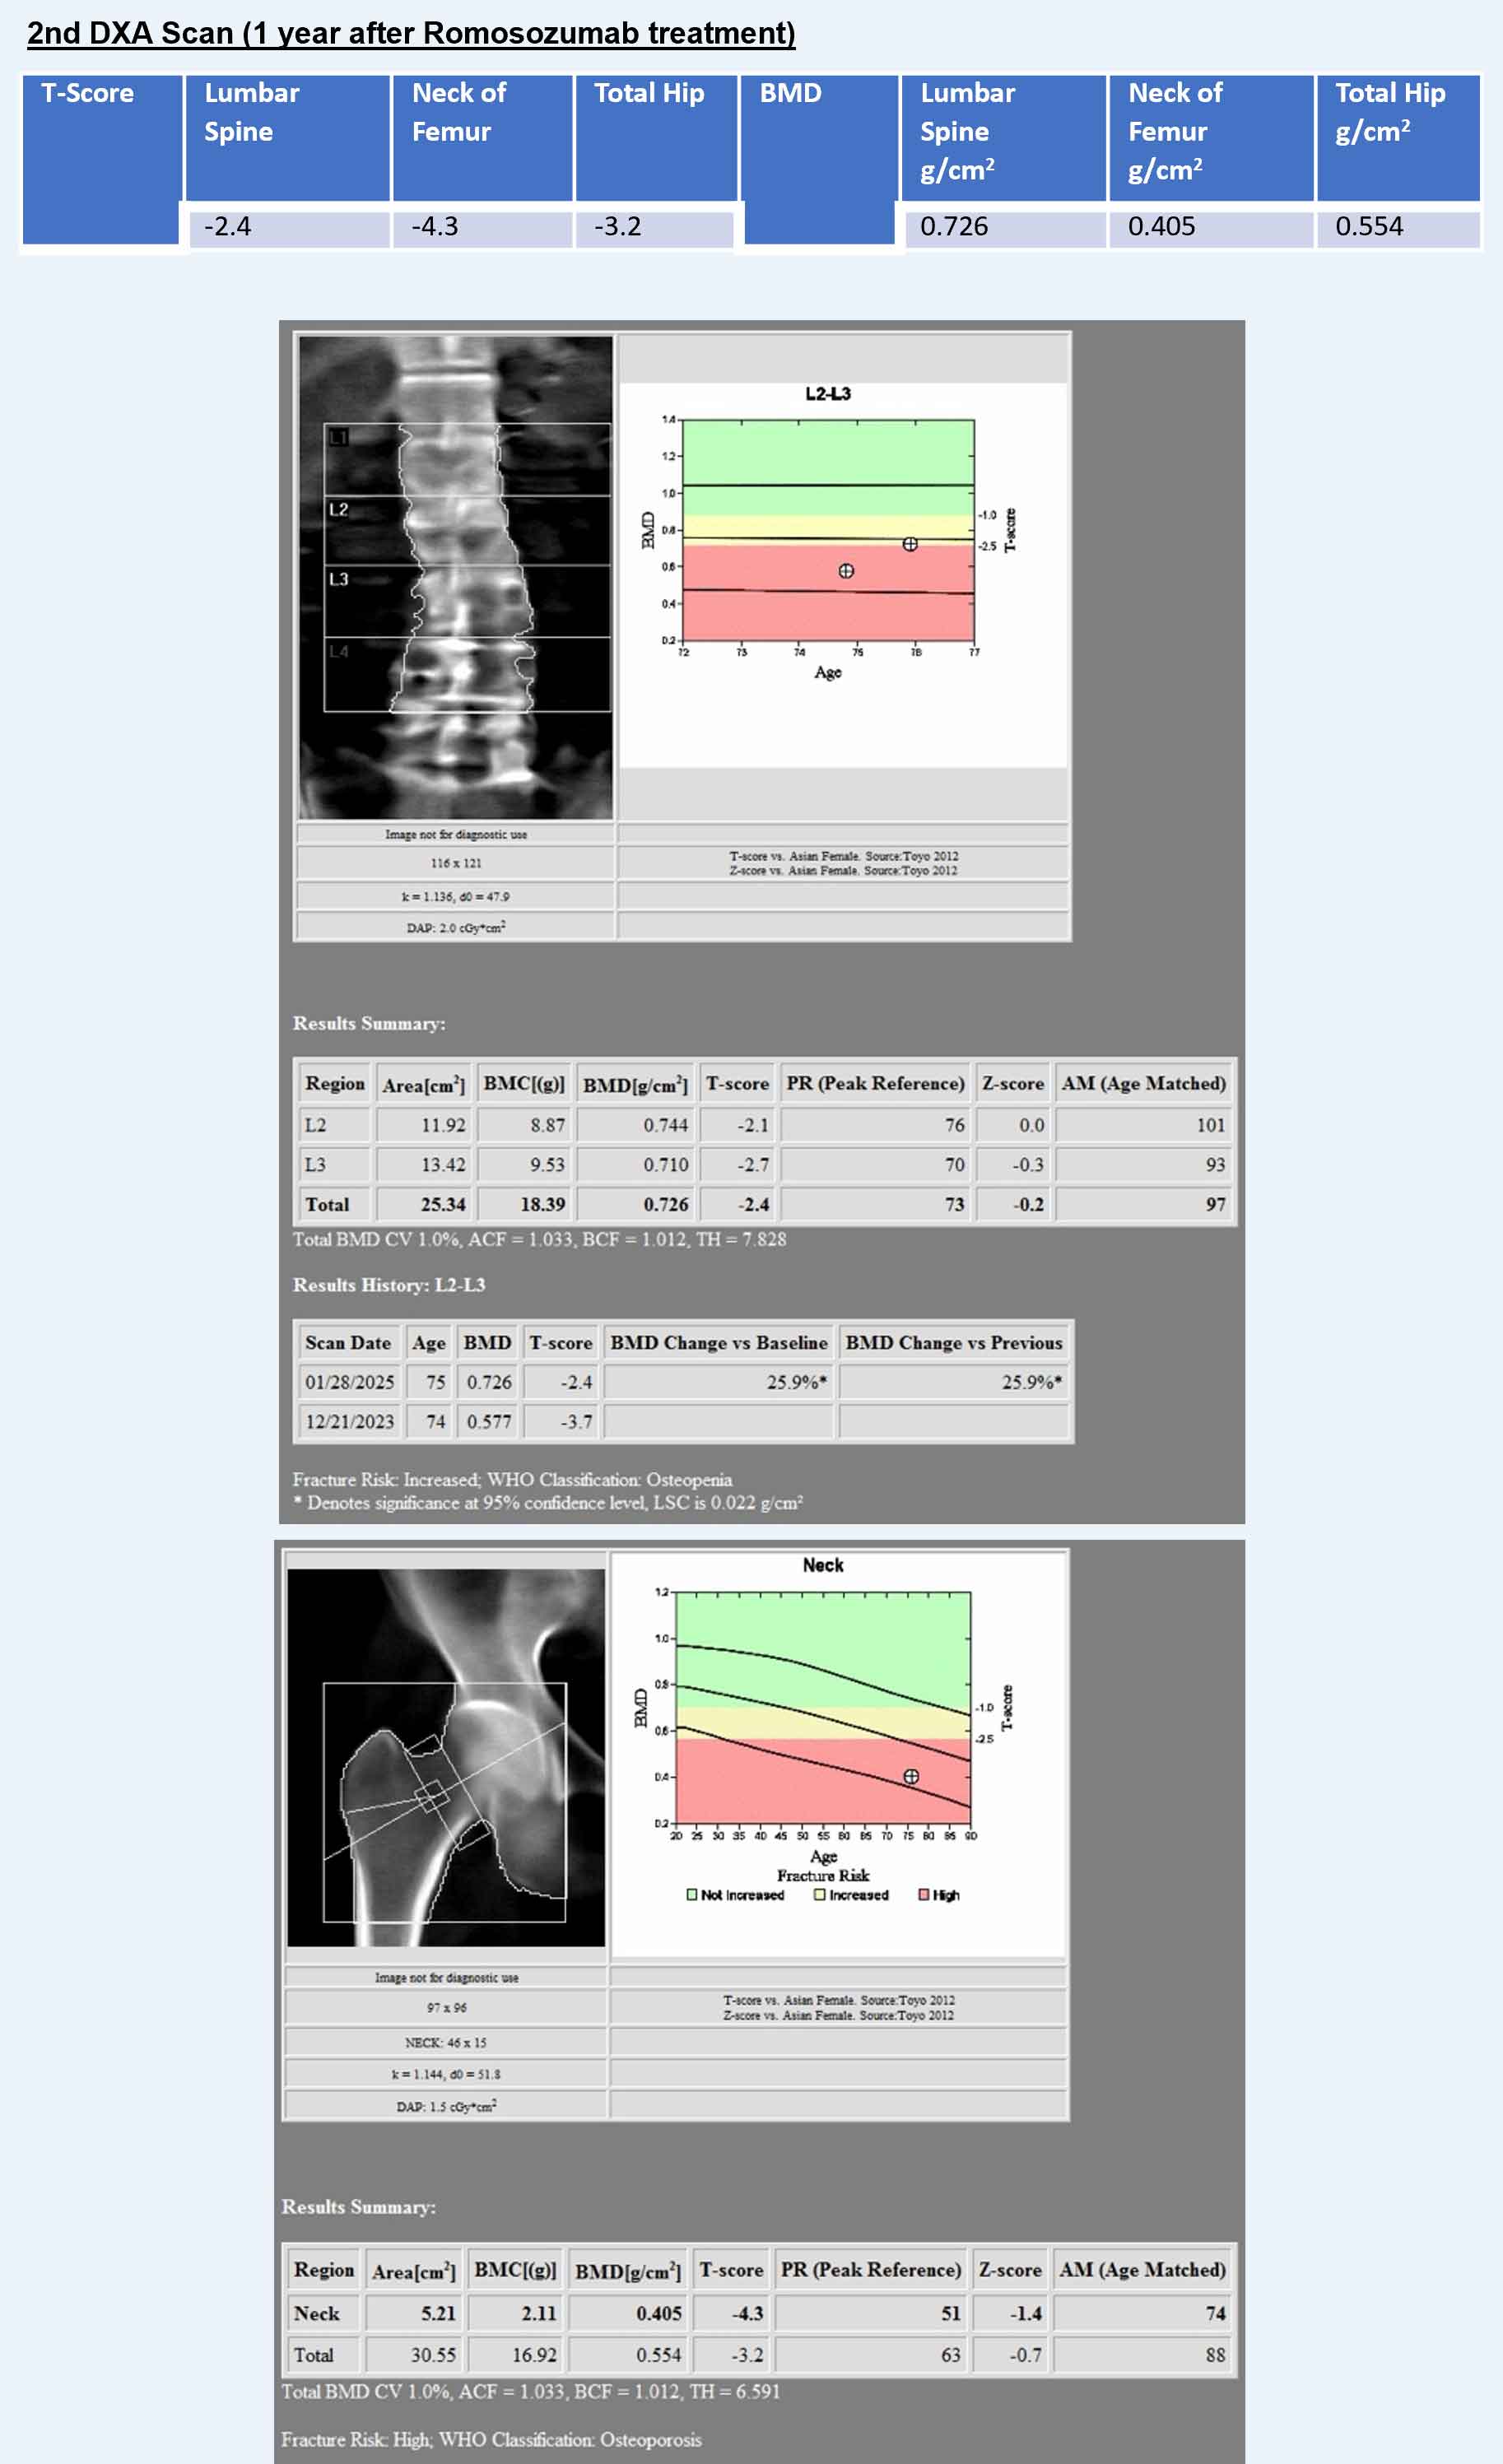

Changes in BMD after completing 1 year of Romosozumab

- Lumbar Spine = +0.149 g/cm2 (25.82%)

- Neck of Femur = +0.058 g/cm2 (16.72%)

- Total Hip = +0.078 g/cm2 (16.39%)

There was an increase in the BMD after she underwent 1 year of treatment with Romosozumab.

- Lumbar Spine: +0.149 g/cm2 (25.82%, LSC 0.022)

- Neck of Femur: +0.058 g/cm2 (16.72%, LSC 0.028)

- Total Hip: +0.078 g/cm2 (16.39%, LSC 0.027)

All the increases in these three parameters were higher than the respective LSC.

- DXA scan showed that the changes in BMD after completing 1 year of romosuzumab was: